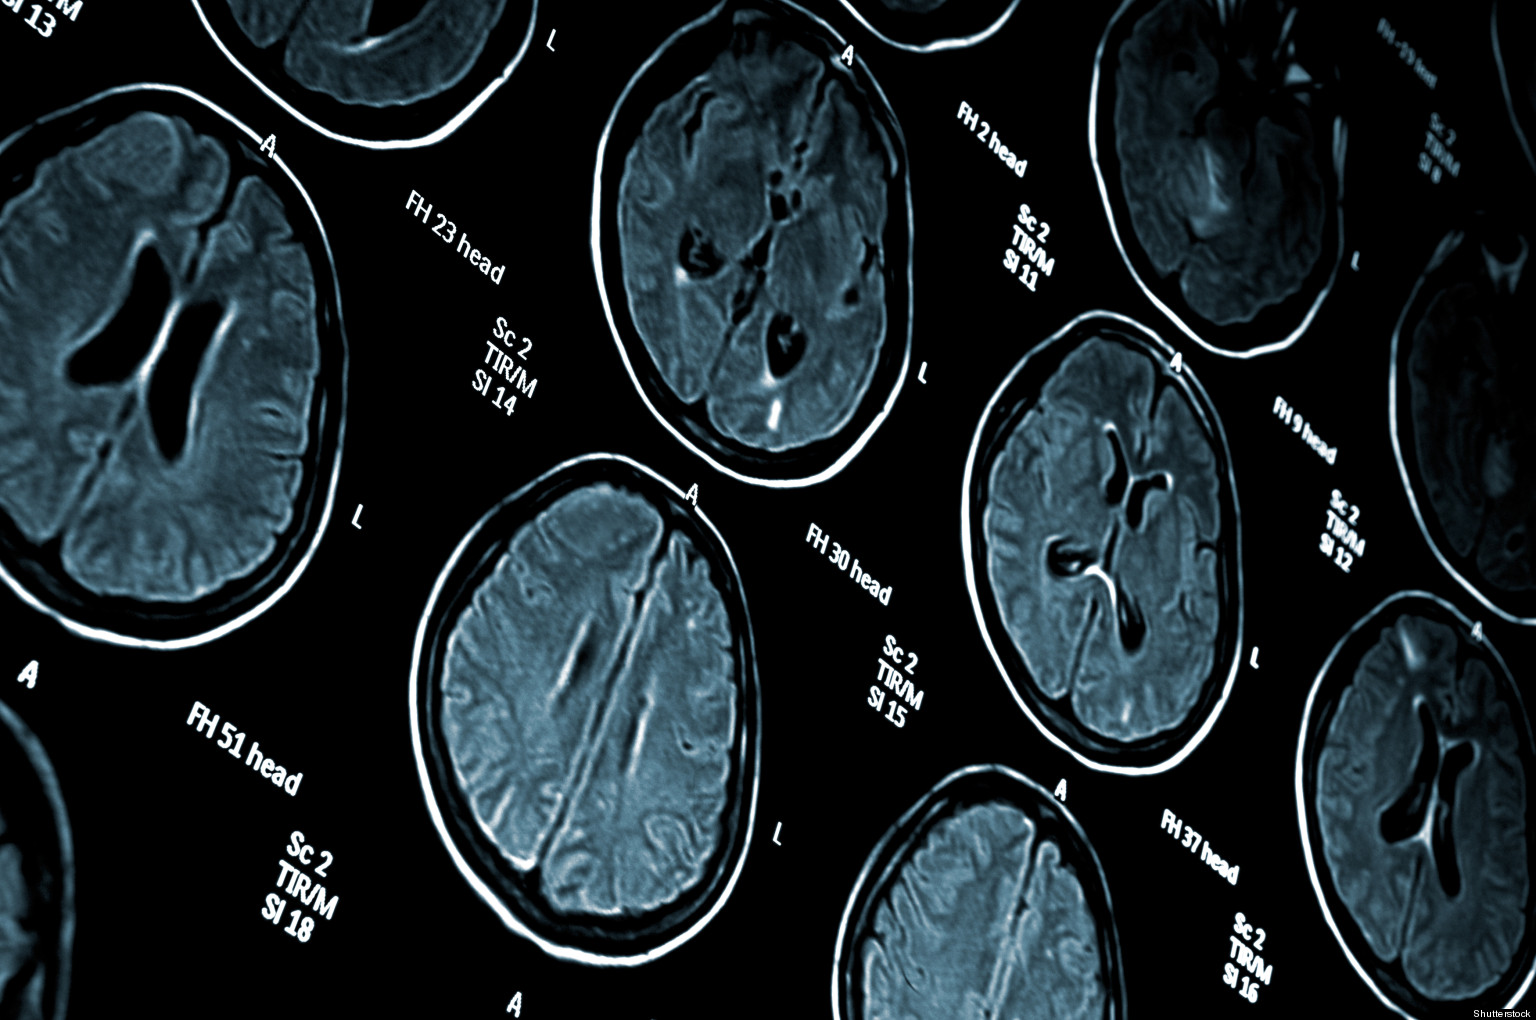

Can Mri Brain Scan Show Depression . An mri scan could reveal what would work for you. And the technology is great at revealing damage from a stroke, or areas that light up when we see a face. Magnetic resonance imaging (mri) studies support reduced brain volume in patients with depression compared to groups of healthy subjects, large. The network identified in depressed people involves many different brain regions. The researchers say that their findings deepen. New mri scans may reveal previously unknown differences in the brains of people with depression. Mri scans have allowed researchers to peer inside the human brain. Functional mri (fmri) brain scans were used to attain 41 activation and connectivity measures for each participant, focussing on six brain circuits known to play a role in. By repeatedly scanning the brains of a small group of patients for a year and a half, weill cornell medicine researchers have identified a. There are no molecular or imaging biomarkers widely accepted for the assessment of clinical depression. Brain imaging combined with machine learning can reveal.

Brain MRI Shows Patterns in Patients with Depression, Anxiety Can Mri Brain Scan Show Depression Mri scans have allowed researchers to peer inside the human brain. New mri scans may reveal previously unknown differences in the brains of people with depression. There are no molecular or imaging biomarkers widely accepted for the assessment of clinical depression. Functional mri (fmri) brain scans were used to attain 41 activation and connectivity measures for each participant, focussing on. Can Mri Brain Scan Show Depression.

MRI scan image of brain Regional Medical Imaging Can Mri Brain Scan Show Depression And the technology is great at revealing damage from a stroke, or areas that light up when we see a face. Functional mri (fmri) brain scans were used to attain 41 activation and connectivity measures for each participant, focussing on six brain circuits known to play a role in. Mri scans have allowed researchers to peer inside the human brain.. Can Mri Brain Scan Show Depression.